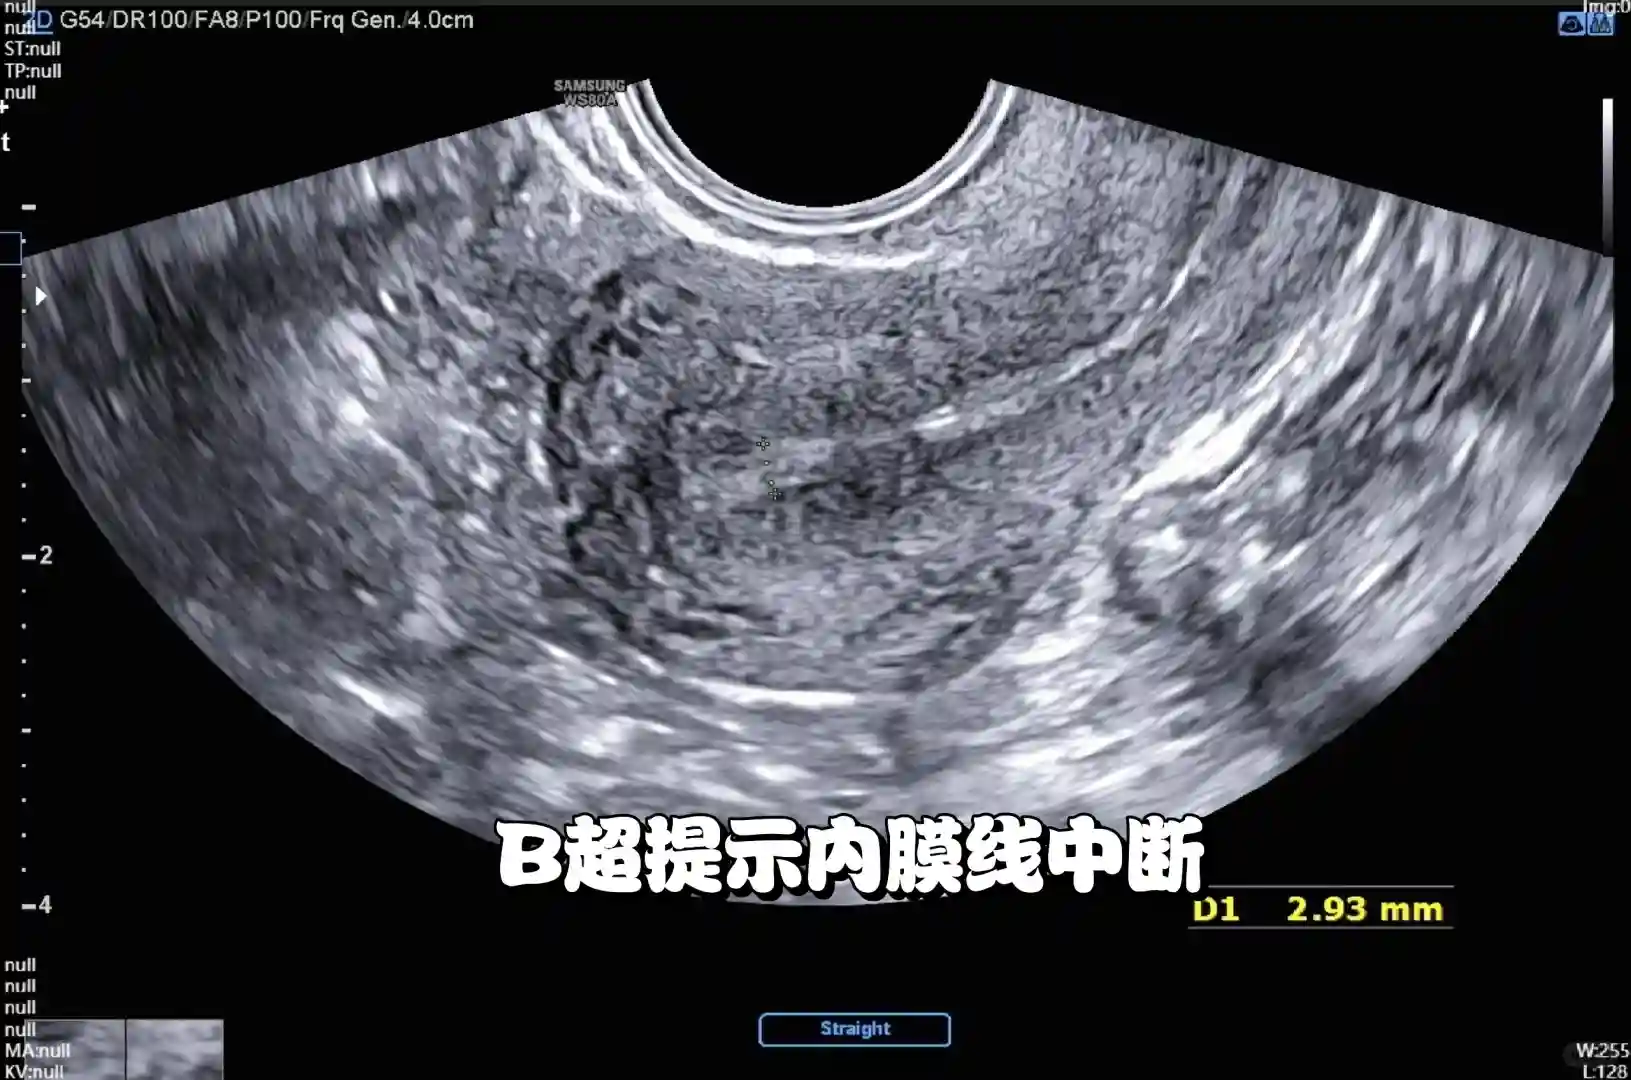

✅ **阴道B超**:初步看内膜厚度,但可能漏诊;

✅ **宫腔镜**:诊断金标准!直接看到粘连部位和程度;